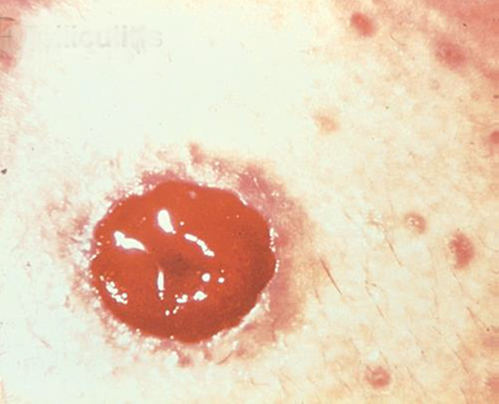

Irritant Dermatitis

Description/Causes:

Inflammation of peristomal skin resulting from contact with stool or urine, usually from leakage under the pouching system.

Symptoms:

- Redness

- Weeping areas of skin